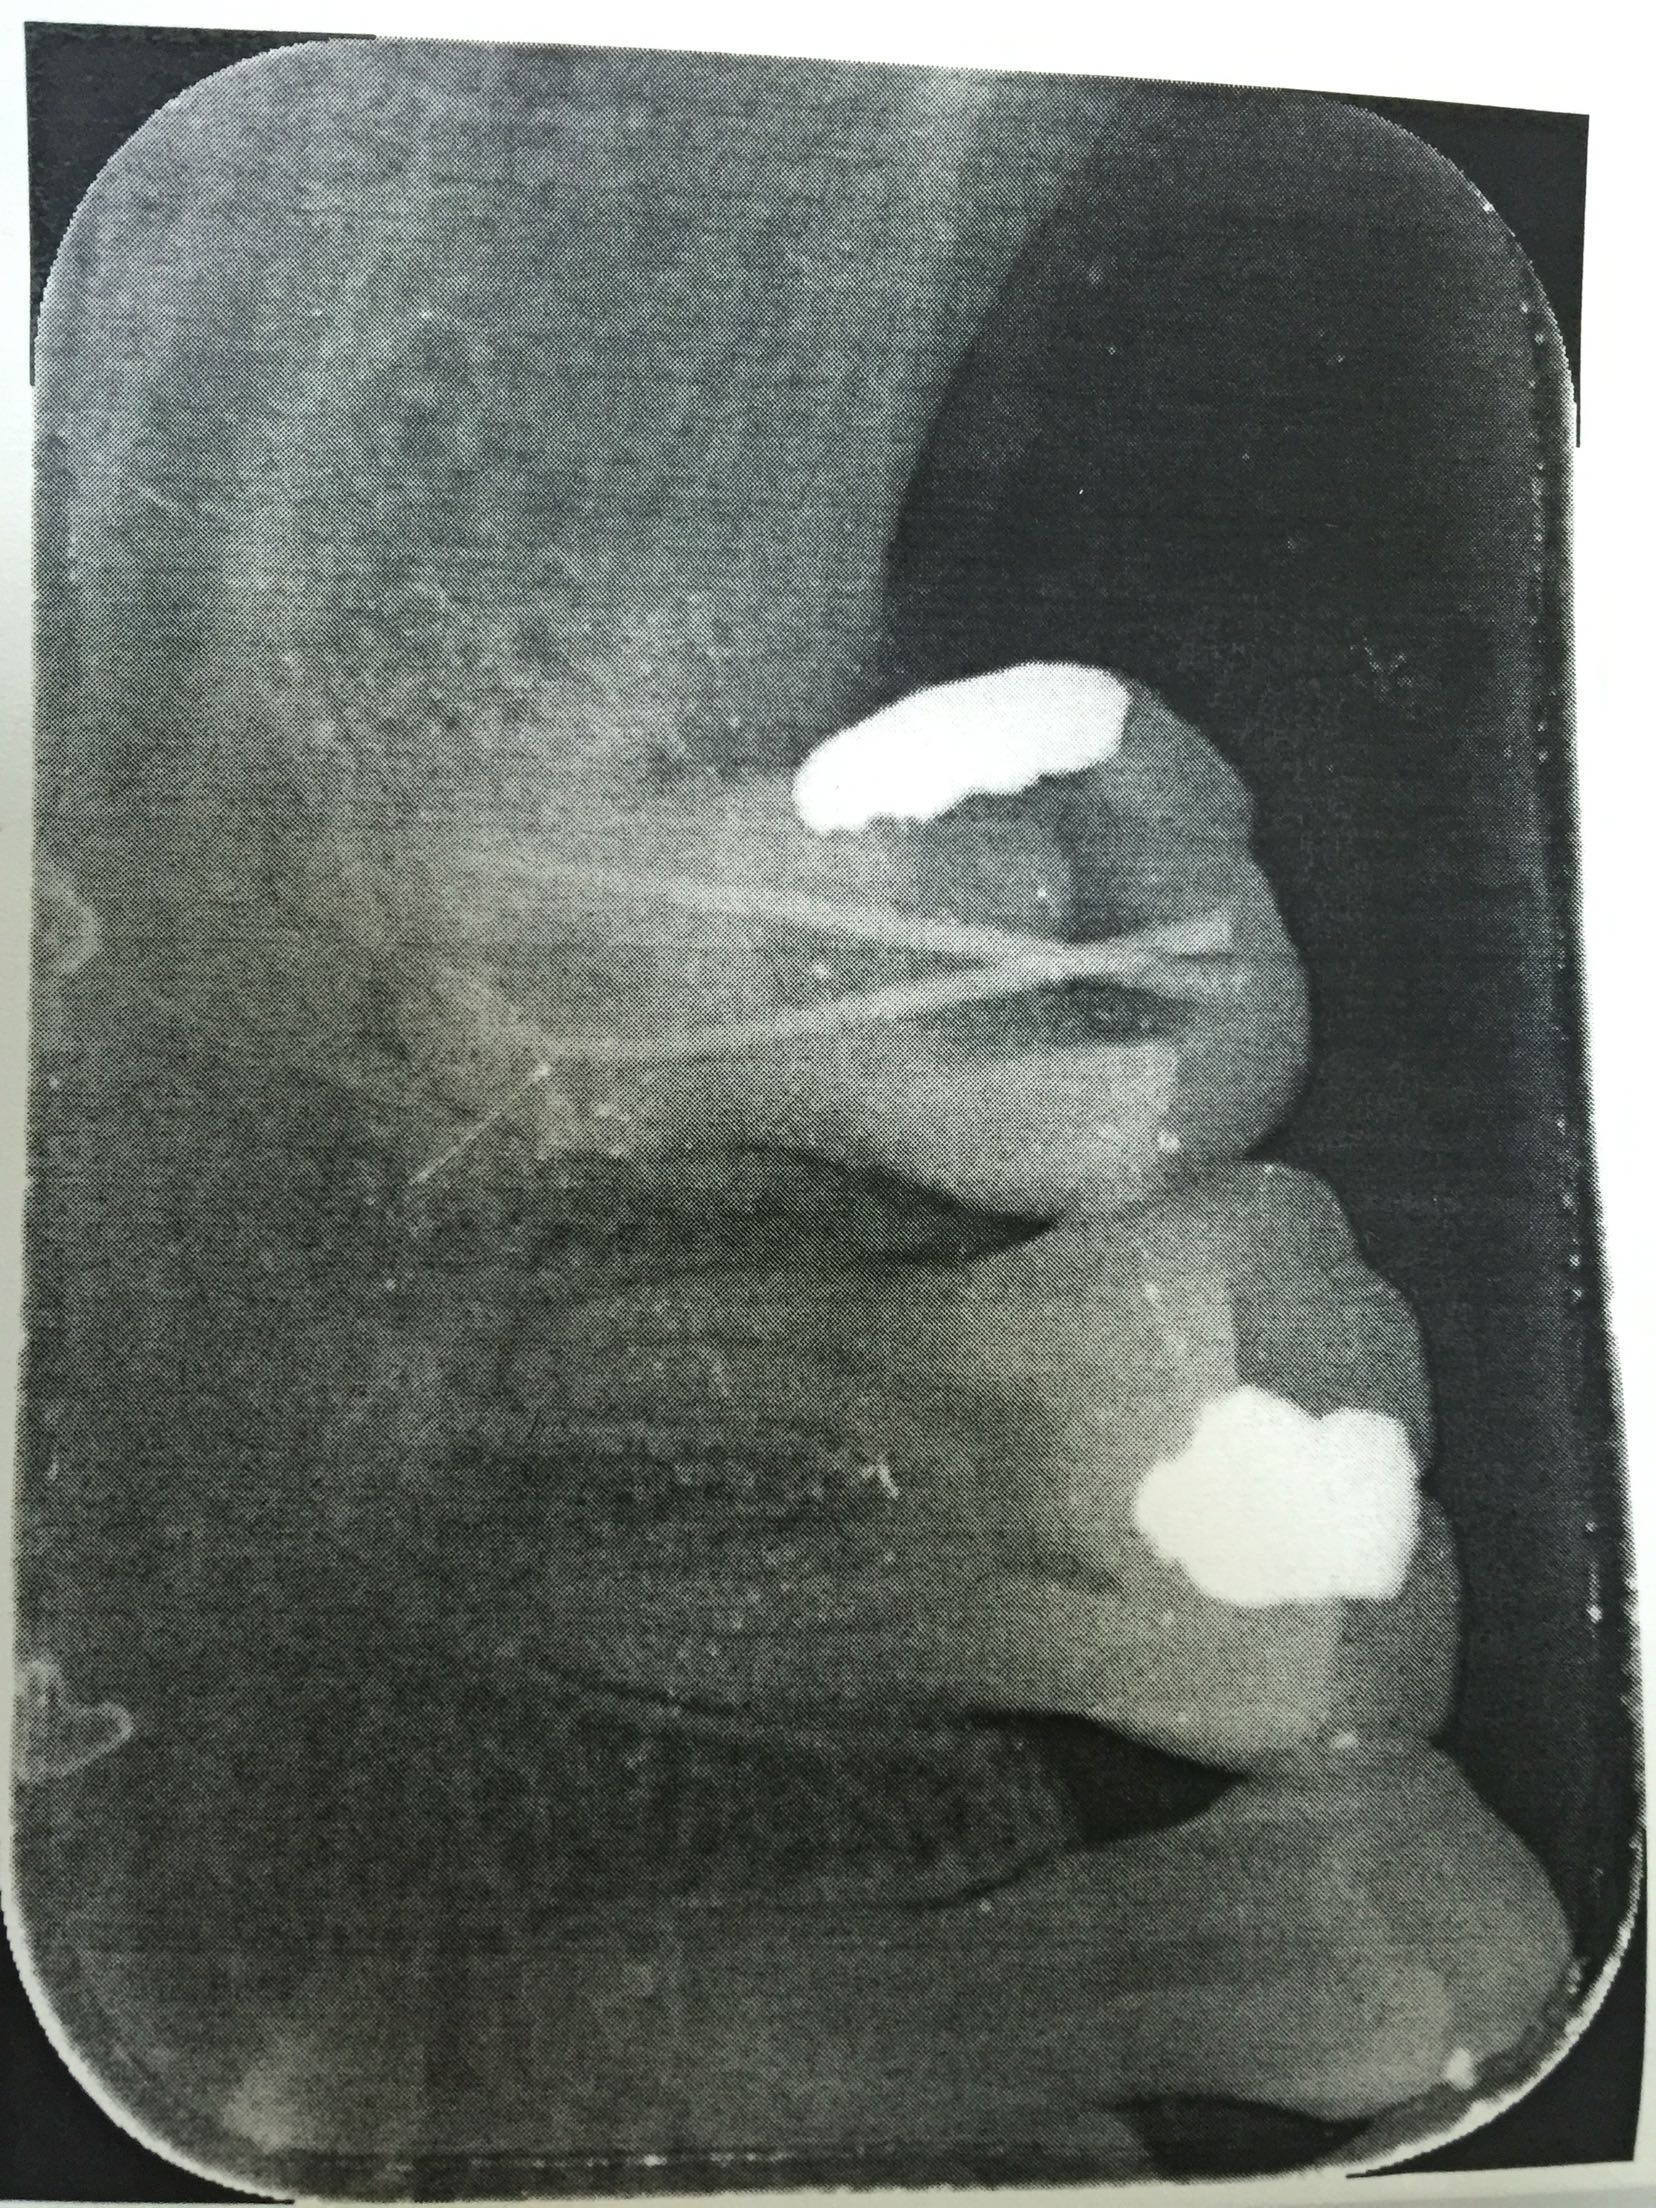

检查:47远中邻合面充填物存,叩诊(+-),松动不明显,牙龈无红肿,冷诊(++)。X线片示:47充填物近髓,根尖未见明显低密度影像。

诊断:47急性牙髓炎 治疗:47局麻下开髓揭顶全,慢失活,暂封,告医嘱,肿痛随诊。 47复诊,无不适。去暂封及失活剂,根管疏通,长度测量,waveone根管预备,冲洗,干燥,根管封药,告医嘱,肿痛随诊。 47复诊,无不适。47常规完成根充,建议冠修复。

此第二磨牙为双根管,也比较常见。下颌第二磨牙变异较大,多见的为C形根,三根管,双根管,单根管都有可能,临床中应注意辨别。